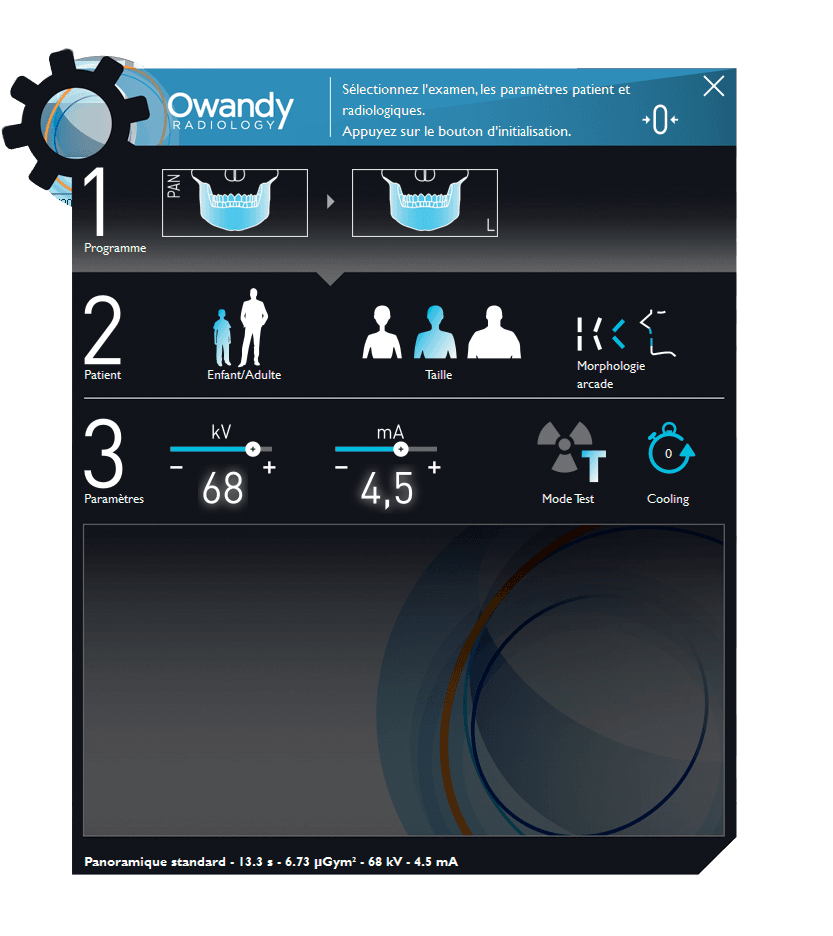

INTUITIVE INTERFACE

Easy to handle unit and related software.

Easy to use

The panoramic unit adapts to suit you and your current needs. It switches easily from the standard 2D version to a 2D/3D Cone Beam mode – whenever you want!

Its intuitive interface makes the I-Max panoramic unit and its operation extremely easy to master.